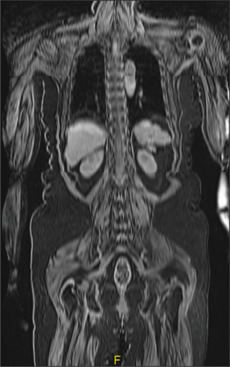

肌萎缩性侧索硬化症(ALS)是一种进行性原发性运动神经元疾病,其病因至今仍有争议。多种遗传和环境因素之间的相互作用以及共存/先行的感染、炎症和恶性肿瘤都被假设为该病的潜在病因。由于其混合诊断能力,氟脱氧葡萄糖正电子发射断层扫描-磁共振成像在检测各种自身免疫性脑炎模式方面具有很高的价值,我们在ALS患者中报道了其中一种,为自身免疫作为该疾病发病机制的潜在病因提供了见解。

Amyotrophic lateral sclerosis (ALS) is a progressive primary motor neuron disorder whose etiology is a subject of debate even today. Interplay between multiple genetic and environmental factors and co-existent/antecedent infection, inflammation, and malignancy have all been hypothesized as potentially causative for this disease. Owing to its hybrid diagnostic capability, fluorodeoxyglucose positron emission tomography-magnetic resonance imaging is highly valuable in detecting varied autoimmune encephalitis patterns, one of which we report in a patient with ALS providing insight into autoimmunity as a potential etiology in the pathogenesis of this disease.